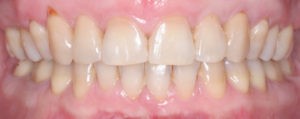

Пациентка, 43 года обратилась в клинику с жалобами на наличие промежутков между зубами, измененный наклон передних зубов верхней челюсти, появившейся за последнее время. Также пациентку беспокоил изменившийся профиль лица.

Для предварительной подготовки были привлечены пародонтолог и ортопед, поскольку отсутствие нескольких зубов, заболевание пародонта и дефекты твердых тканей зубов сопутствовали основной патологии. Проведены пародонтологические процедуры, вылечен кариес и его осложнения, изготовлены временные коронки для зубов с большим разрушением. На фото — временные коронки на боковых зубах.

Пациентка довольна профилем и красивой улыбкой.